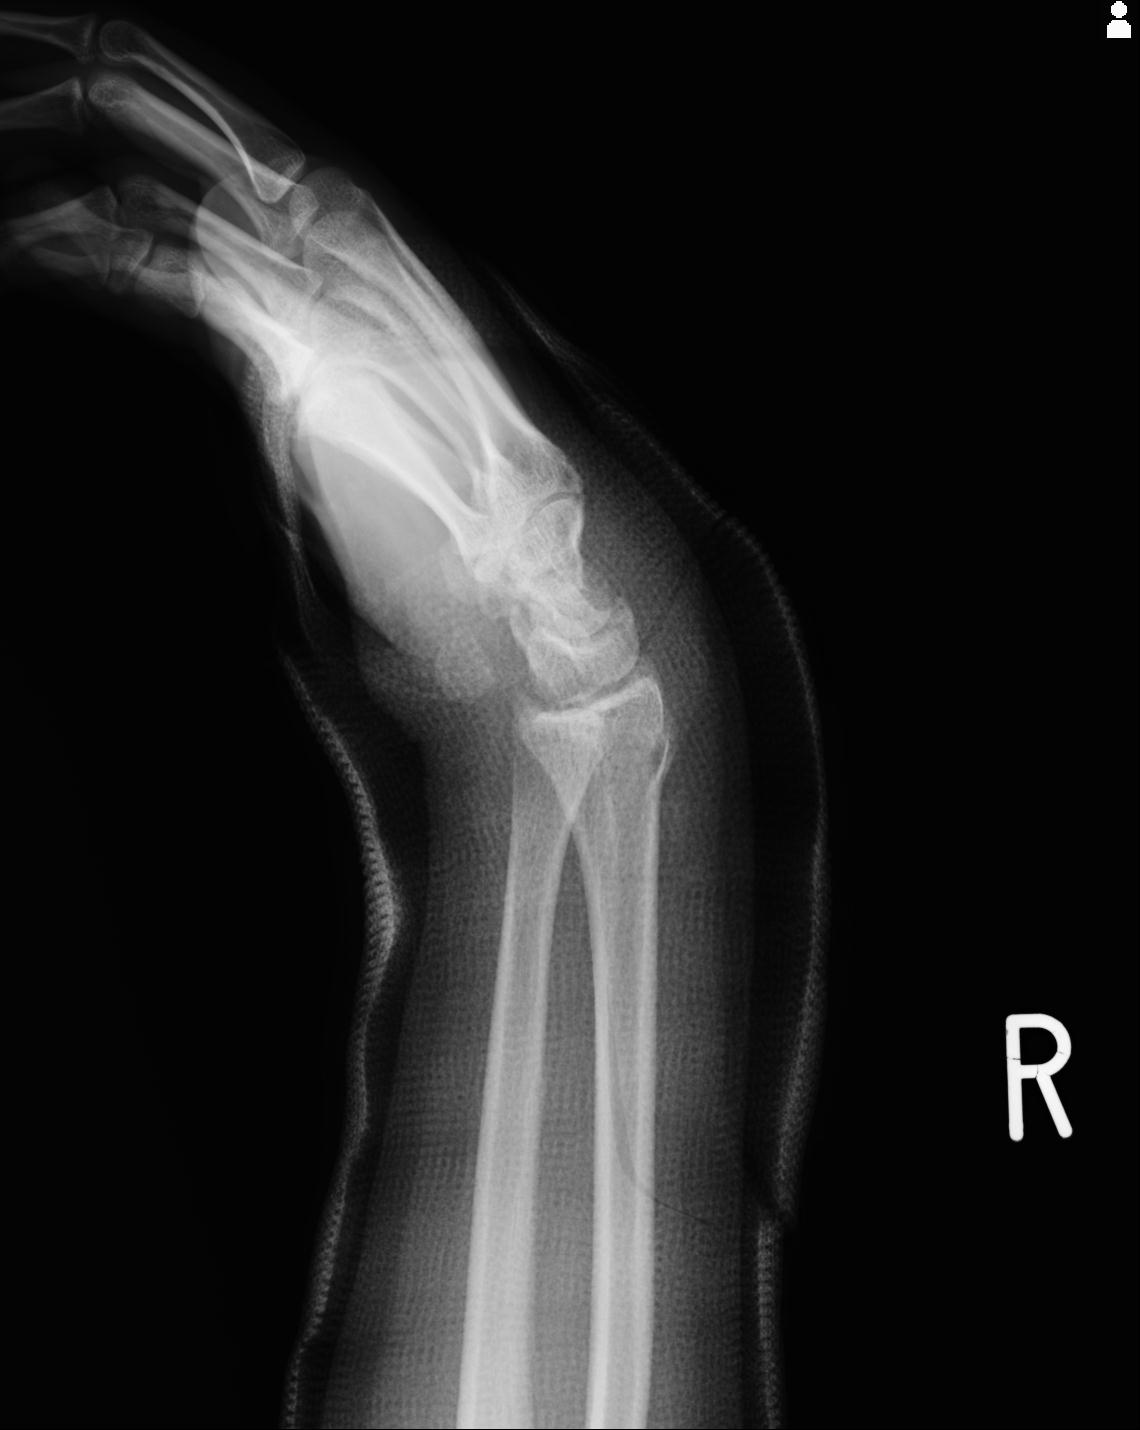

50435 1/4 1/15 手関節 4R 17歳女性 右橈骨遠位端